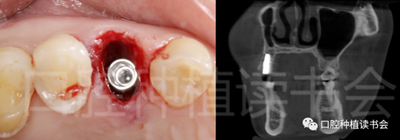

5.3.3 根據(jù)拔牙窩內(nèi)的牙槽間隔高度,植入康盛CANSUN柱形親水種植體(4.3*8mm),確保種植體肩臺與牙槽間隔平齊,種植體的所有表面均被自體骨包繞(圖16),植入扭矩為25N.cm。

圖16 盡量讓種植體表面被牙槽間隔的自體骨包繞。

5.3.5 考慮到初始植入扭矩未達(dá)到30N.cm,采用外覆”倍菱“膠原蛋白+縫線固定的方式關(guān)閉創(chuàng)口的方案(圖18)。

圖18 創(chuàng)口使用”倍菱“膠原蛋白保護(hù),促進(jìn)愈合。